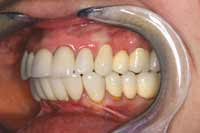

The patient returned 1 month later for computerized occlusal analysis. The analysis objectively confirmed that the occlusion was balanced and right and left cuspid disclusion as well as protrusion were immediate and measurable to less than 0.2 seconds. The patient was reevaluated at 6 months, 1 year, and 3 years posttreatment. Her symptoms have not returned. Follow-up examinations using biometric instrumentation objectively show normal healthy muscle function, normal jaw function, normal swallowing, and a normal airway. The patient is ecstatic with her final result (Figure 17 through Figure 19).

Figure 17 Completed case, right-side view.

Figure 18 Completed case, left-side view.

Figure 19 Completed case. The patient was pleased with her final smile